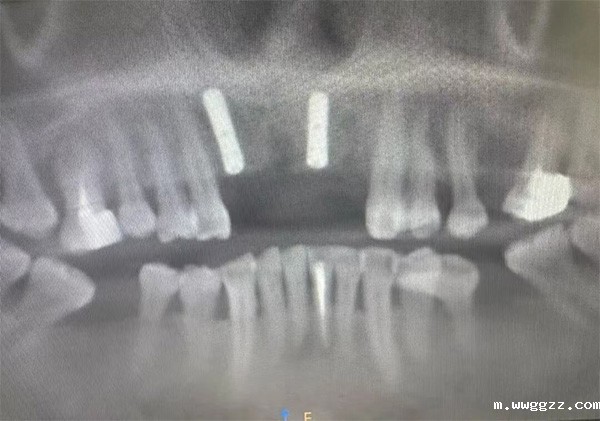

本次带教聚焦一例高难度上前牙连续多颗牙缺失病例。患者为48岁女性,原11、12、21、22牙位烤瓷冠脱落,11、21缺失,12、22牙体预备术后,II度松动。CBCT示:12根尖处见椭圆形低密度影像,边界清晰。11、12、21、22牙槽骨条件欠佳。对前牙美学与功能恢复有着极高要求。

本组病例为一例48岁女性患者,因“上前牙区反复肿胀一月”就诊。临床检查见11、12、21牙体存留,呈Ⅱ度松动,唇侧黏膜可见瘘管口。CBCT影像显示:11、12根尖区见一椭圆形低密度透射影,边界清晰,囊肿范围偏腭侧延伸,11、21牙根远中1/3位于囊腔内部,解剖关系复杂,手术难度较高。